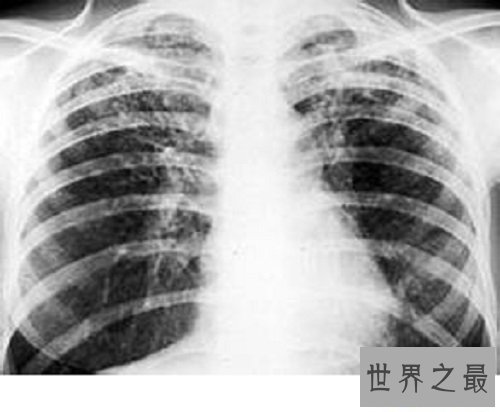

胸部X线显示两中下肺野网状暗影,肺性能为限度性通气性能阻碍。病情呈继续性进展,最终因呼吸衰竭而死亡。起病藏匿,停止性加重。体现为停止性气急,干咳少痰或大批白黏痰,晚期出现以低氧血症为主的呼吸衰竭。查体可见胸廓呼吸静止减弱,双肺可闻及细湿罗音或捻发音。有不同水平紫绀和杵状指。晚期可出现右心衰竭体征。